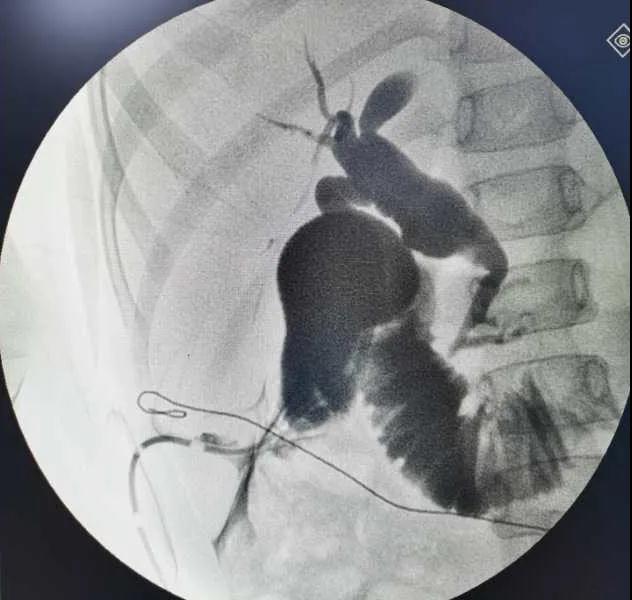

5月7日,西安國際醫學中心醫院小兒外科郭正團教授團隊成功為1名膽總管囊腫患兒進行了腹腔鏡膽管造影 腹腔鏡膽總管囊腫切除 腹腔鏡肝管空腸吻合術。目前,患兒恢復良好,已正常進食。

入院后,謝崇醫生積極為患兒完善術前準備,MRCP(核磁共振膽道水成像)顯示該患兒為膽總管囊腫Ic型,有明顯的胰膽合流異常。面對復雜的病情,小兒外科郭正團主任立即組織團隊進行術前討論,制定了完善的手術方案及應急措施。

5月7日,一切準備就緒,郭正團主任主刀,帶領小兒外科團隊進行腹腔鏡膽管造影 腹腔鏡膽總管囊腫切除 腹腔鏡肝管空腸吻合術。術中,患兒膽總管與周圍肝動脈及門靜脈粘連嚴重,給手術增加了難度。郭正團主任沉著冷靜,操作嫻熟,完整剝離了膽總管囊腫及遠端胰腺段膽管,肝總管與空腸完成了Roux-en-Y吻合,手術進行順利。術后第2天,玲玲就可以下床活動;第6天,已正常飲食。